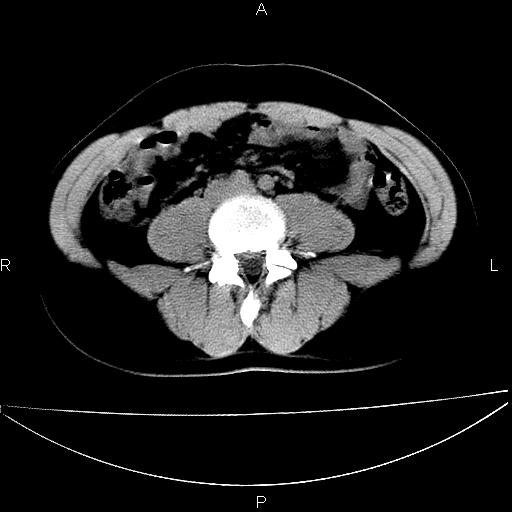

男 25岁 自述 尿频尿急,排尿困难20多天.无腰痛, b超说左肾盂轻度积水,左输尿管上端扩张.未见结石影. ct我看双侧肾盂轻度积水,双输尿管上端都扩张,大家看看能看见结石吗?

双肾轻度积水,双侧输尿管上段扩张(原因待查)。

双输尿管扩张下端未见高密度结石和输尿管晕轮征,不好说是结石.增强后如何?

双肾盂及双输尿上段轻度积水,双输尿管未见明显结石影。